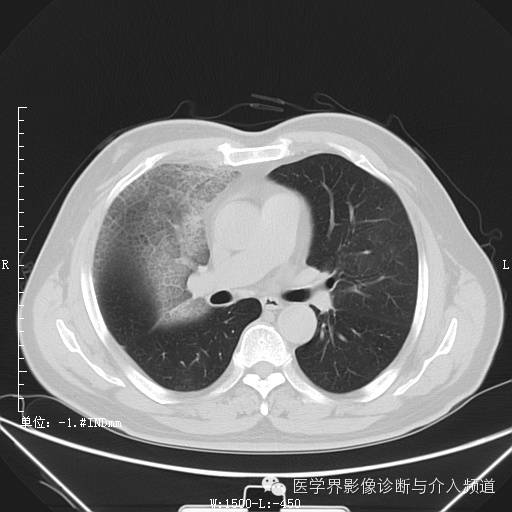

二次复查

二次复查:双肺多发实变、磨玻璃结构及粟粒结节,较前病变范围明显增大右侧并发气胸。